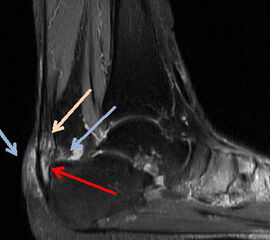

MRT

Abbildung 4: Das MRT des Rückfusses zeigt die unterschiedlichen Veränderungen, die mit einer Insertionstendinopathie einhergehen. Die präachilläre und retrocalcaneare Bursitiden (Pfeile) kommen zur Darstellung, sowie die intratendinösen Veränderungen.

Abbildung 4

Das MRT stellt den Goldstandard bei der Beurteilung von Sehnen und Weichteilgeweben dar. Die optimalen Sequenzen hängen häufig von dem verwendeten Gerät ab, zumeist werden jedoch T1-gewichtete und flüssigkeitssensitive STIR sowie Fett supprimierte intermediär gewichtete Sequenzen in axialer und sagittaler Schnittführung durchgeführt 12.  Das MRT ermöglicht insbesondere den Nachweis von intratendinösen Veränderungen und ansatznahen Partialrupturen. Daneben können im MRT das Paratenon, die ansatznahen Bursen und auch die differerentialdiagnostisch in Frage kommenden Strukturen wie die FHL-Sehne und das Os trigonum mitbeurteilt werden. Ein Ödem in der Tuberositas des Calcaneus kann degenerative Veränderungen der Gleitfläche zur  Achillessehne hin anzeigen. Aufgrund der Schnittführung und des zum Teil geringen Kontrastes ist die Identifikation und Lokalisation von Ossifikationen jedoch gelegentlich zur operativen Planung nicht ausreichend (Abb 4).